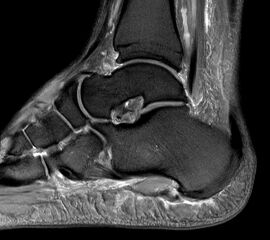

Abbildung 1: Plantarer und dorsaler Sporn im Röntgenbild und im MRT

Abb. 1a und Abb. 1b: großer dorsaler Fersensporn und ein minimaler plantarer Sporn, Patient, 50 Jahre.

Abb. 1c: Bild eines isolierten großen plantaren Fersensporns. Patientin, 32 Jahre.

Zum Lesen der Bildbeschreibung und zur Vollansicht bitte die Bilder anklicken. Bilder: Manfred Thomas.